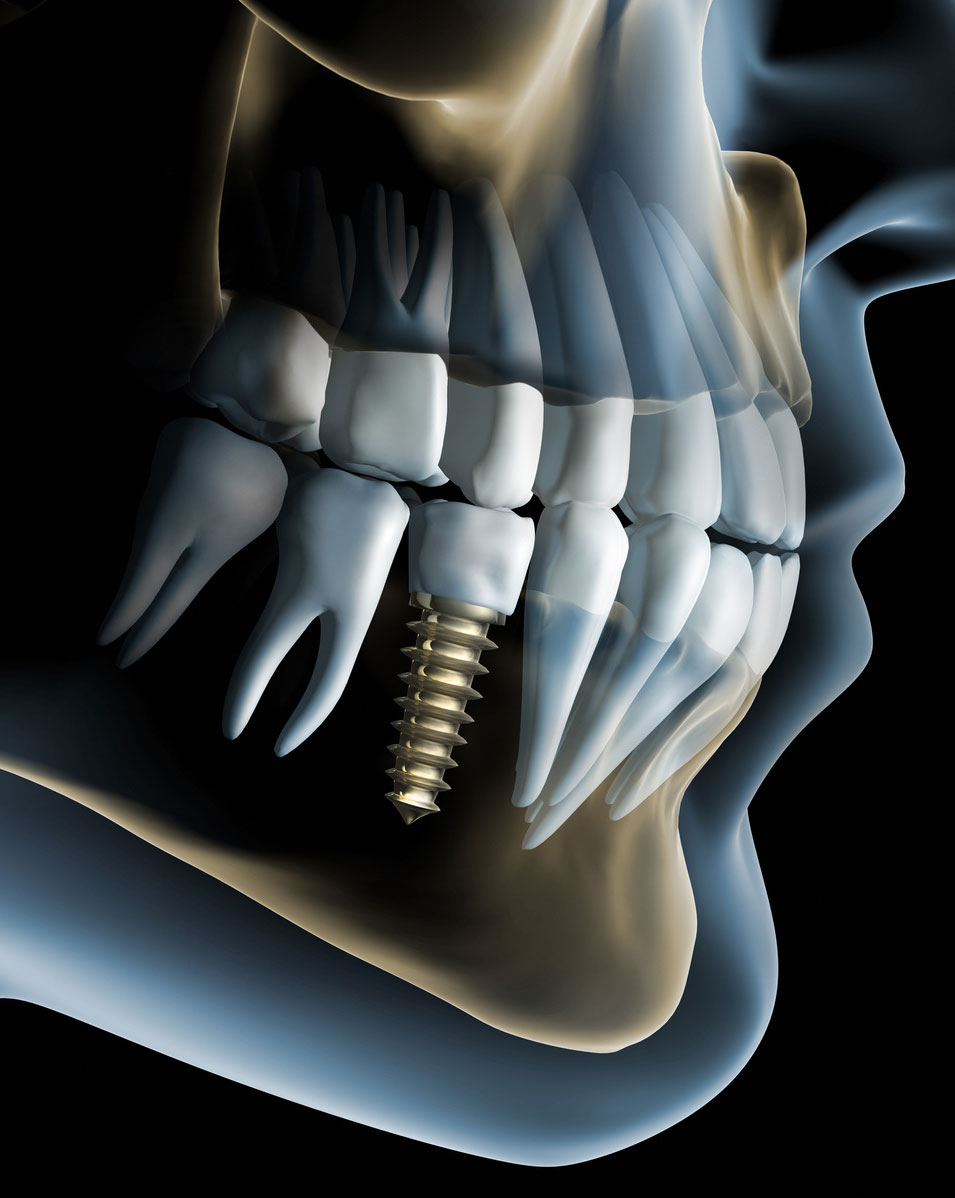

Implantologia avanzata

L'implantologia moderna nasce grazie alle scoperte di Branemark che scoprì la capacità dell'osso di crescere e aderire sulle superfici di titanio. Oggi grazie a questa scoperta si possono sostituire strutture ossee in qualsiasi distretto del corpo anche la bocca. Le viti in titanio possono sostituire le radici di denti persi e corone dentarie possono essere montate sulle viti integrate con una resa funzionale ed estetica eccellente.

Da più di venticinque anni lo studio dentistico dei dottori Valenti utilizza tecniche chirurgiche e implantari per il ripristino di una funzione masticatoria con protesi fisse su impianti osteointegrati. I nostri pazienti in questo modo non sono costretti ad accettare protesi totali o parziali removibili aumentando incredibilmente il comfort masticatorio e psicologico. Sono sempre più frequenti i casi in cui viene realizzata nella stessa seduta l'estrazione dei denti (se ancora presenti e irrimediabilmente persi), il posizionamento degli impianti e la protesi immediata (il paziente riceve gli impianti che vengono nella stessa seduta protesizzati).

Gli interventi chirurgici per il posizionamento degli impianti vengono effettuati con una attenzione estrema al benessere e al confort del paziente cercando di ridurre al minimo qualsiasi traumatismo potendo così ridurre al minimo i periodi di recupero. Inoltre vi è la possibilità di eseguire gli interventi in Sedazione Cosciente (vedi sotto) garantendo un esperienza anche psicologiamente del tutto atraumatica. Come per i denti anche gli impianti devono essere mantenuti con una ottima igiene orale e i controlli periodici. Anche gli impianti infatti possono essere soggetti a infezioni dei tessuti di supporto (perimplantiti).

I pazienti che si sottopongono a interventi per l'inserimento di impianti in titanio vengono seguiti molto da vicino per dare loro un aiuto nel mantenimento dell'igiene orale domiciliare presupposto fondamentale per la longevità delle protesi su impianti.